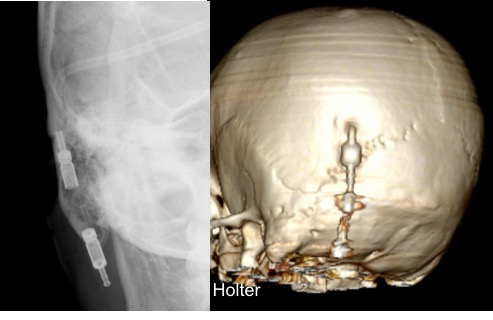

il existe un grand nombre de valves ; il n’est pas toujours aisé de les reconnaitre radiologiquement. voici la liste des plus courantes :

comment reconnaitre radiologiquement le type de valve ?

il est important pour le radiologue qui fait une IRM quel est le type de valve en raison des implications sur l’image et sur le fonctionnement de la valve (en pratique ce surtout les anciennes sophysas ancien modèle qui se dérèglent dans l’IRM).